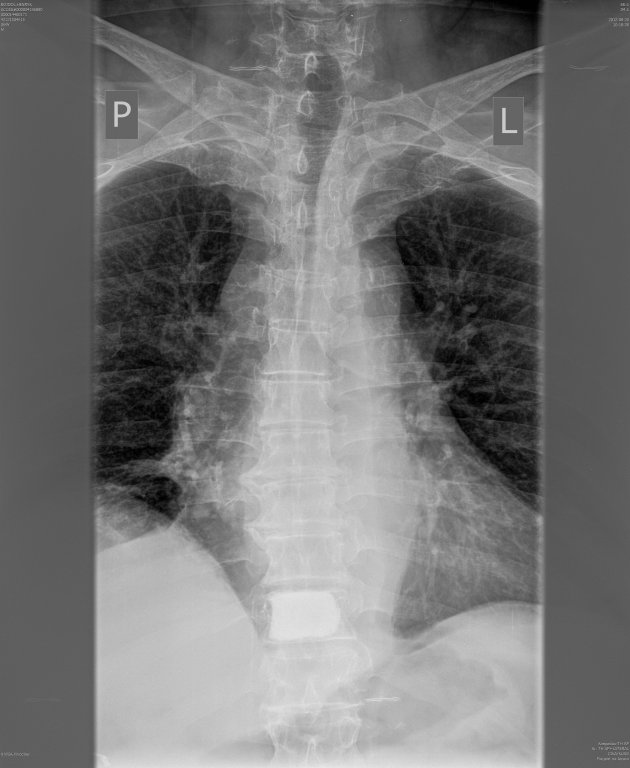

WERTEBROPLASTYKA trzonu TH-10